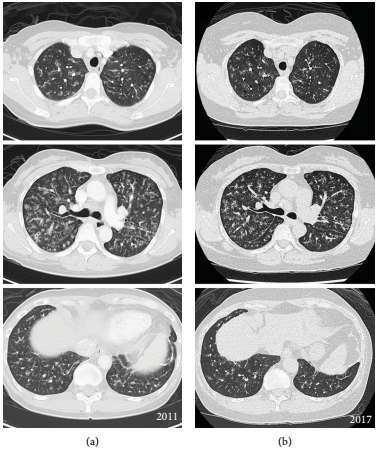

十年前,一位53岁的女性在进行选择性子宫切除术的术前评估时意外发现胸片异常。根据高分辨率计算机断层扫描(HRCT)(图1a)和肺活检报告,诊断为LIP,肺小叶间隔明显纤维化,弥漫性间质和细支气管周围淋巴浆细胞浸润,伴有散在的嗜酸性粒细胞。患者没有接受任何治疗,随后两年没有进行随访。

6年后,患者因8个月的咳嗽和呼吸困难病史就诊。6分钟步行距离为440 m,血氧饱和度为89%,肺功能试验(PFT)显示限制性,FEV1 53%,FVC 67%,DLCO 70%。重复HRCT显示弥漫性支气管血管周围增厚和磨玻璃样改变,双肺支气管血管束沿线有小囊肿(图1b)。

图1. LIP的初次扫描(a)和6年后(b)的选定轴向CT图像